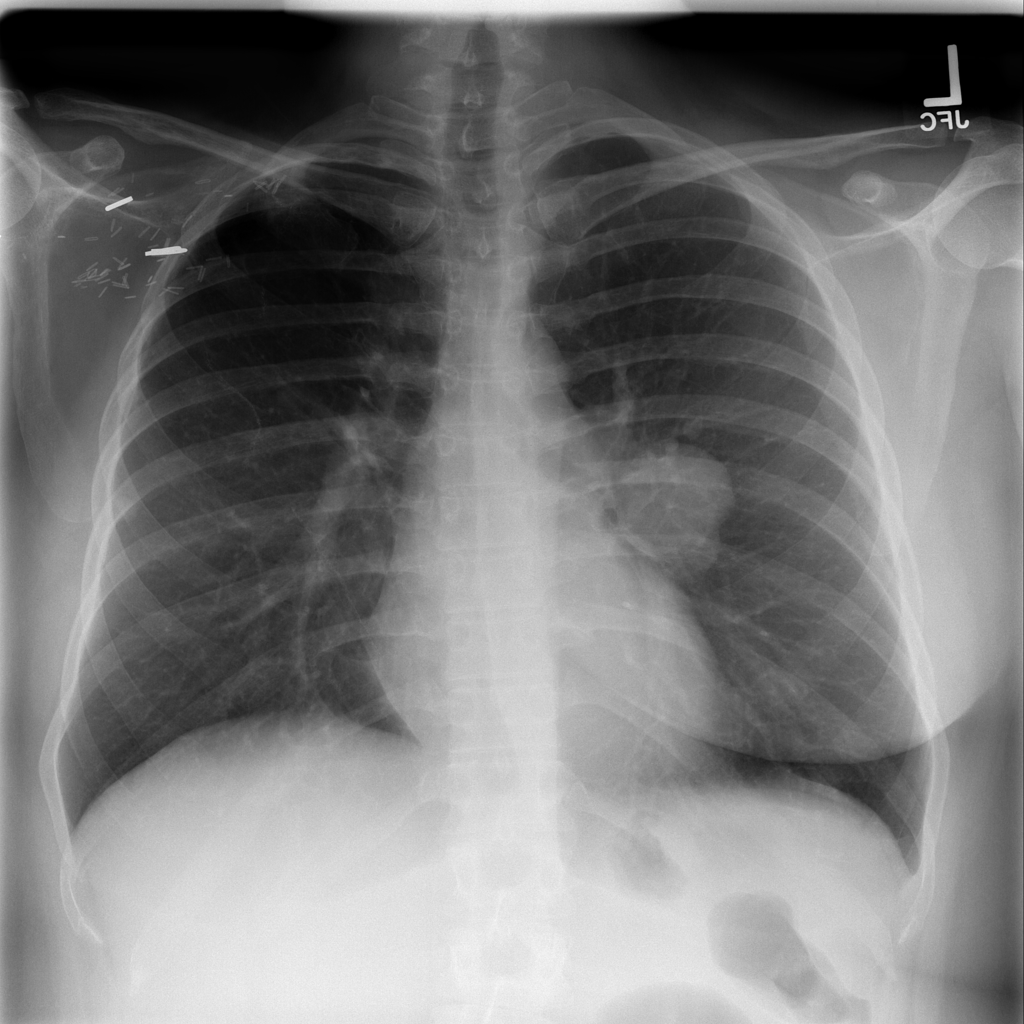

PAT-C0E5 · IMG-001Mass

PAT-C0E5 · IMG-001

PA